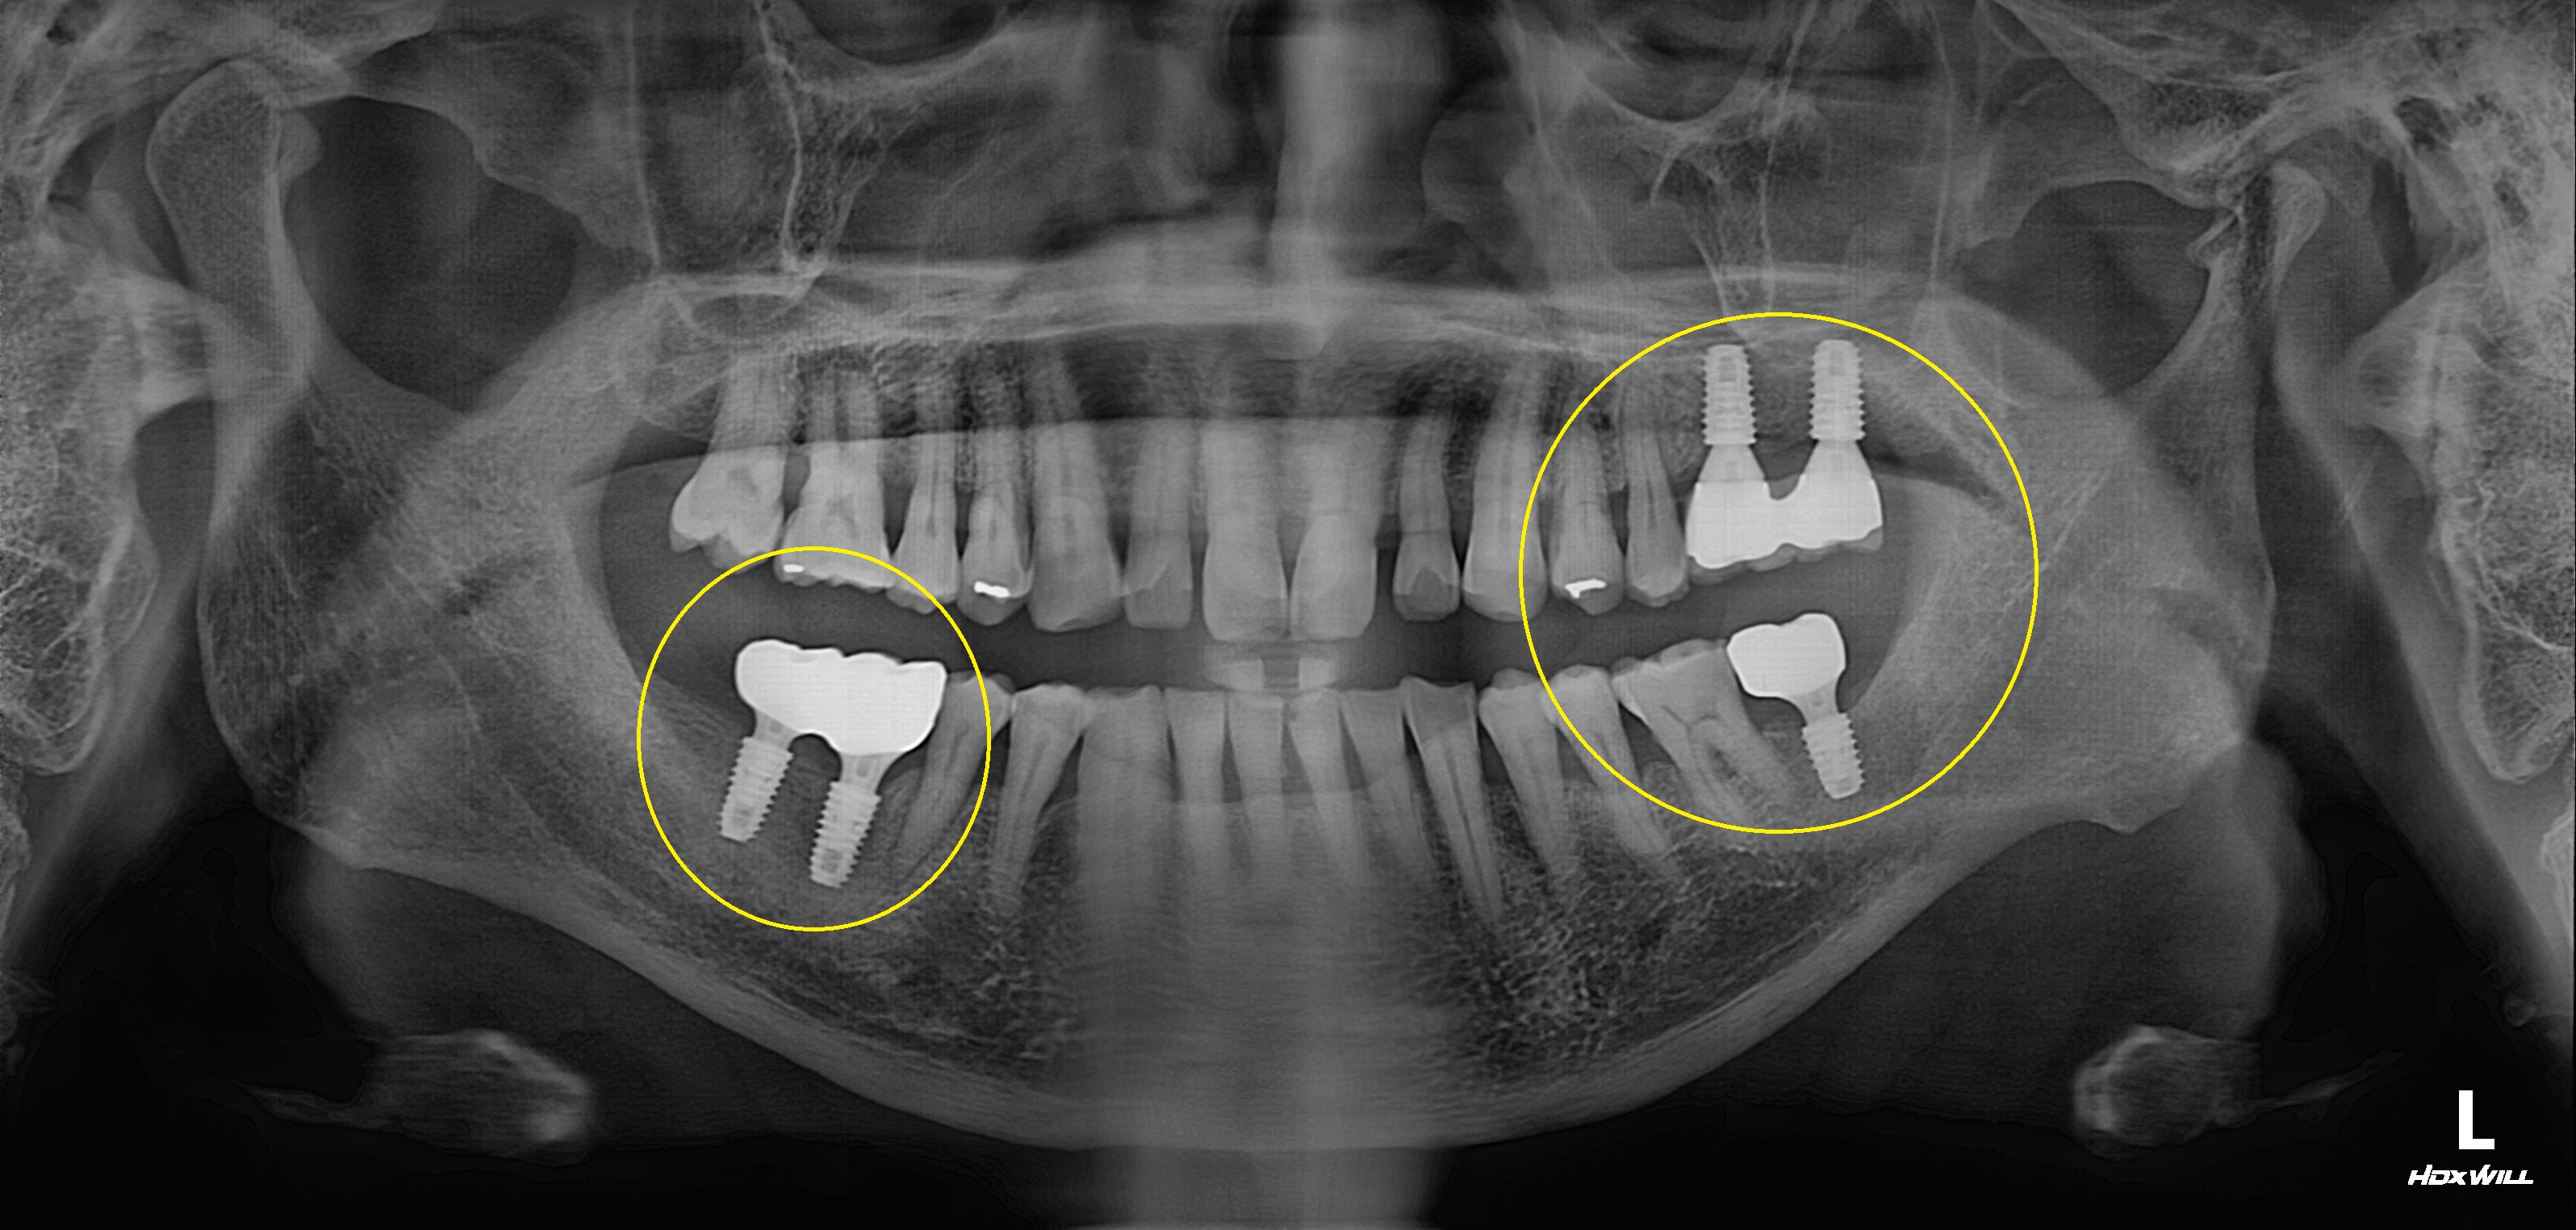

수술 전

수술 후

구치부 임플란트 식립사례

전후사진